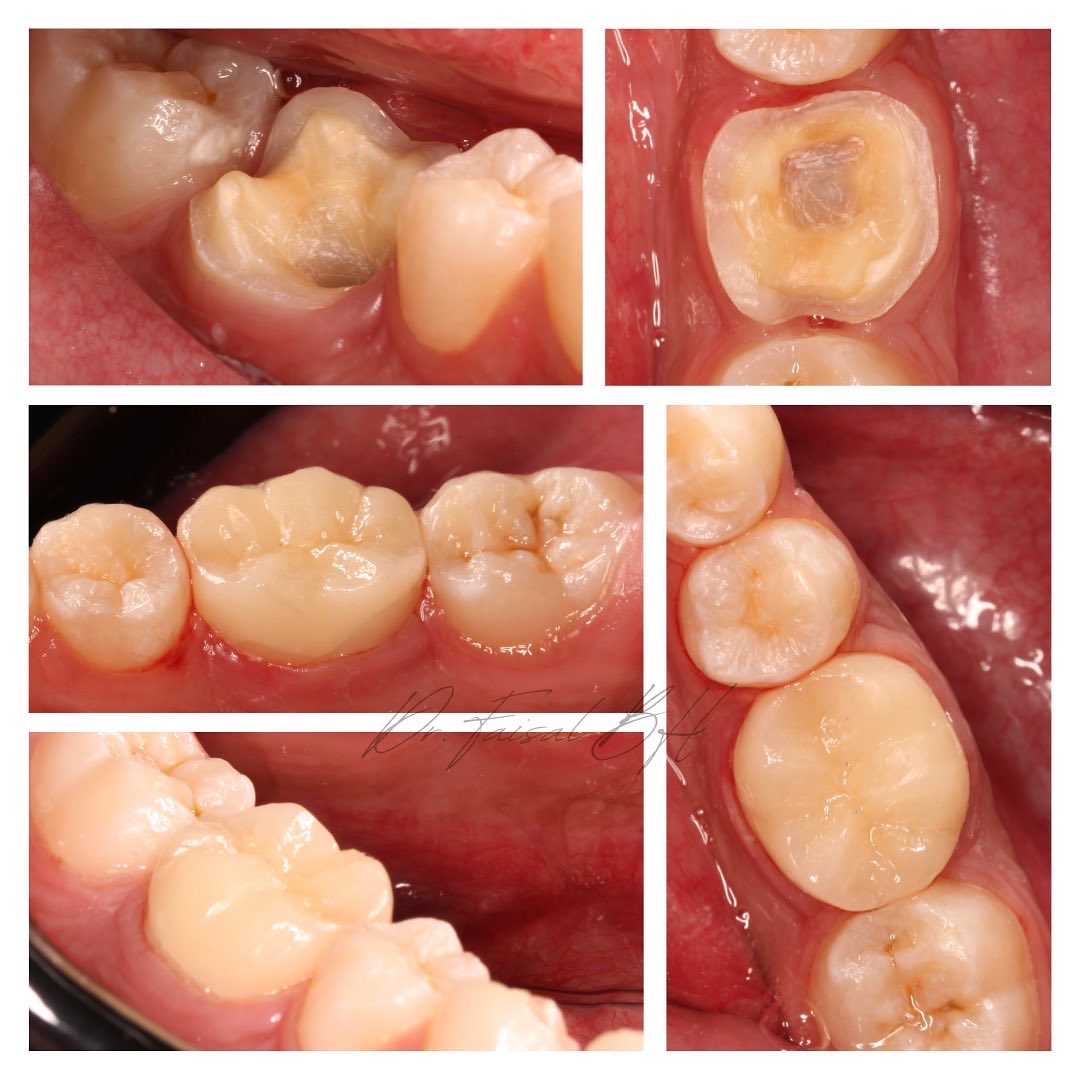

تلبيسة للطاحن السفلي الأول #46

Endo-Crown for Tooth #46

Lithium disilicate (e.max) Bonded